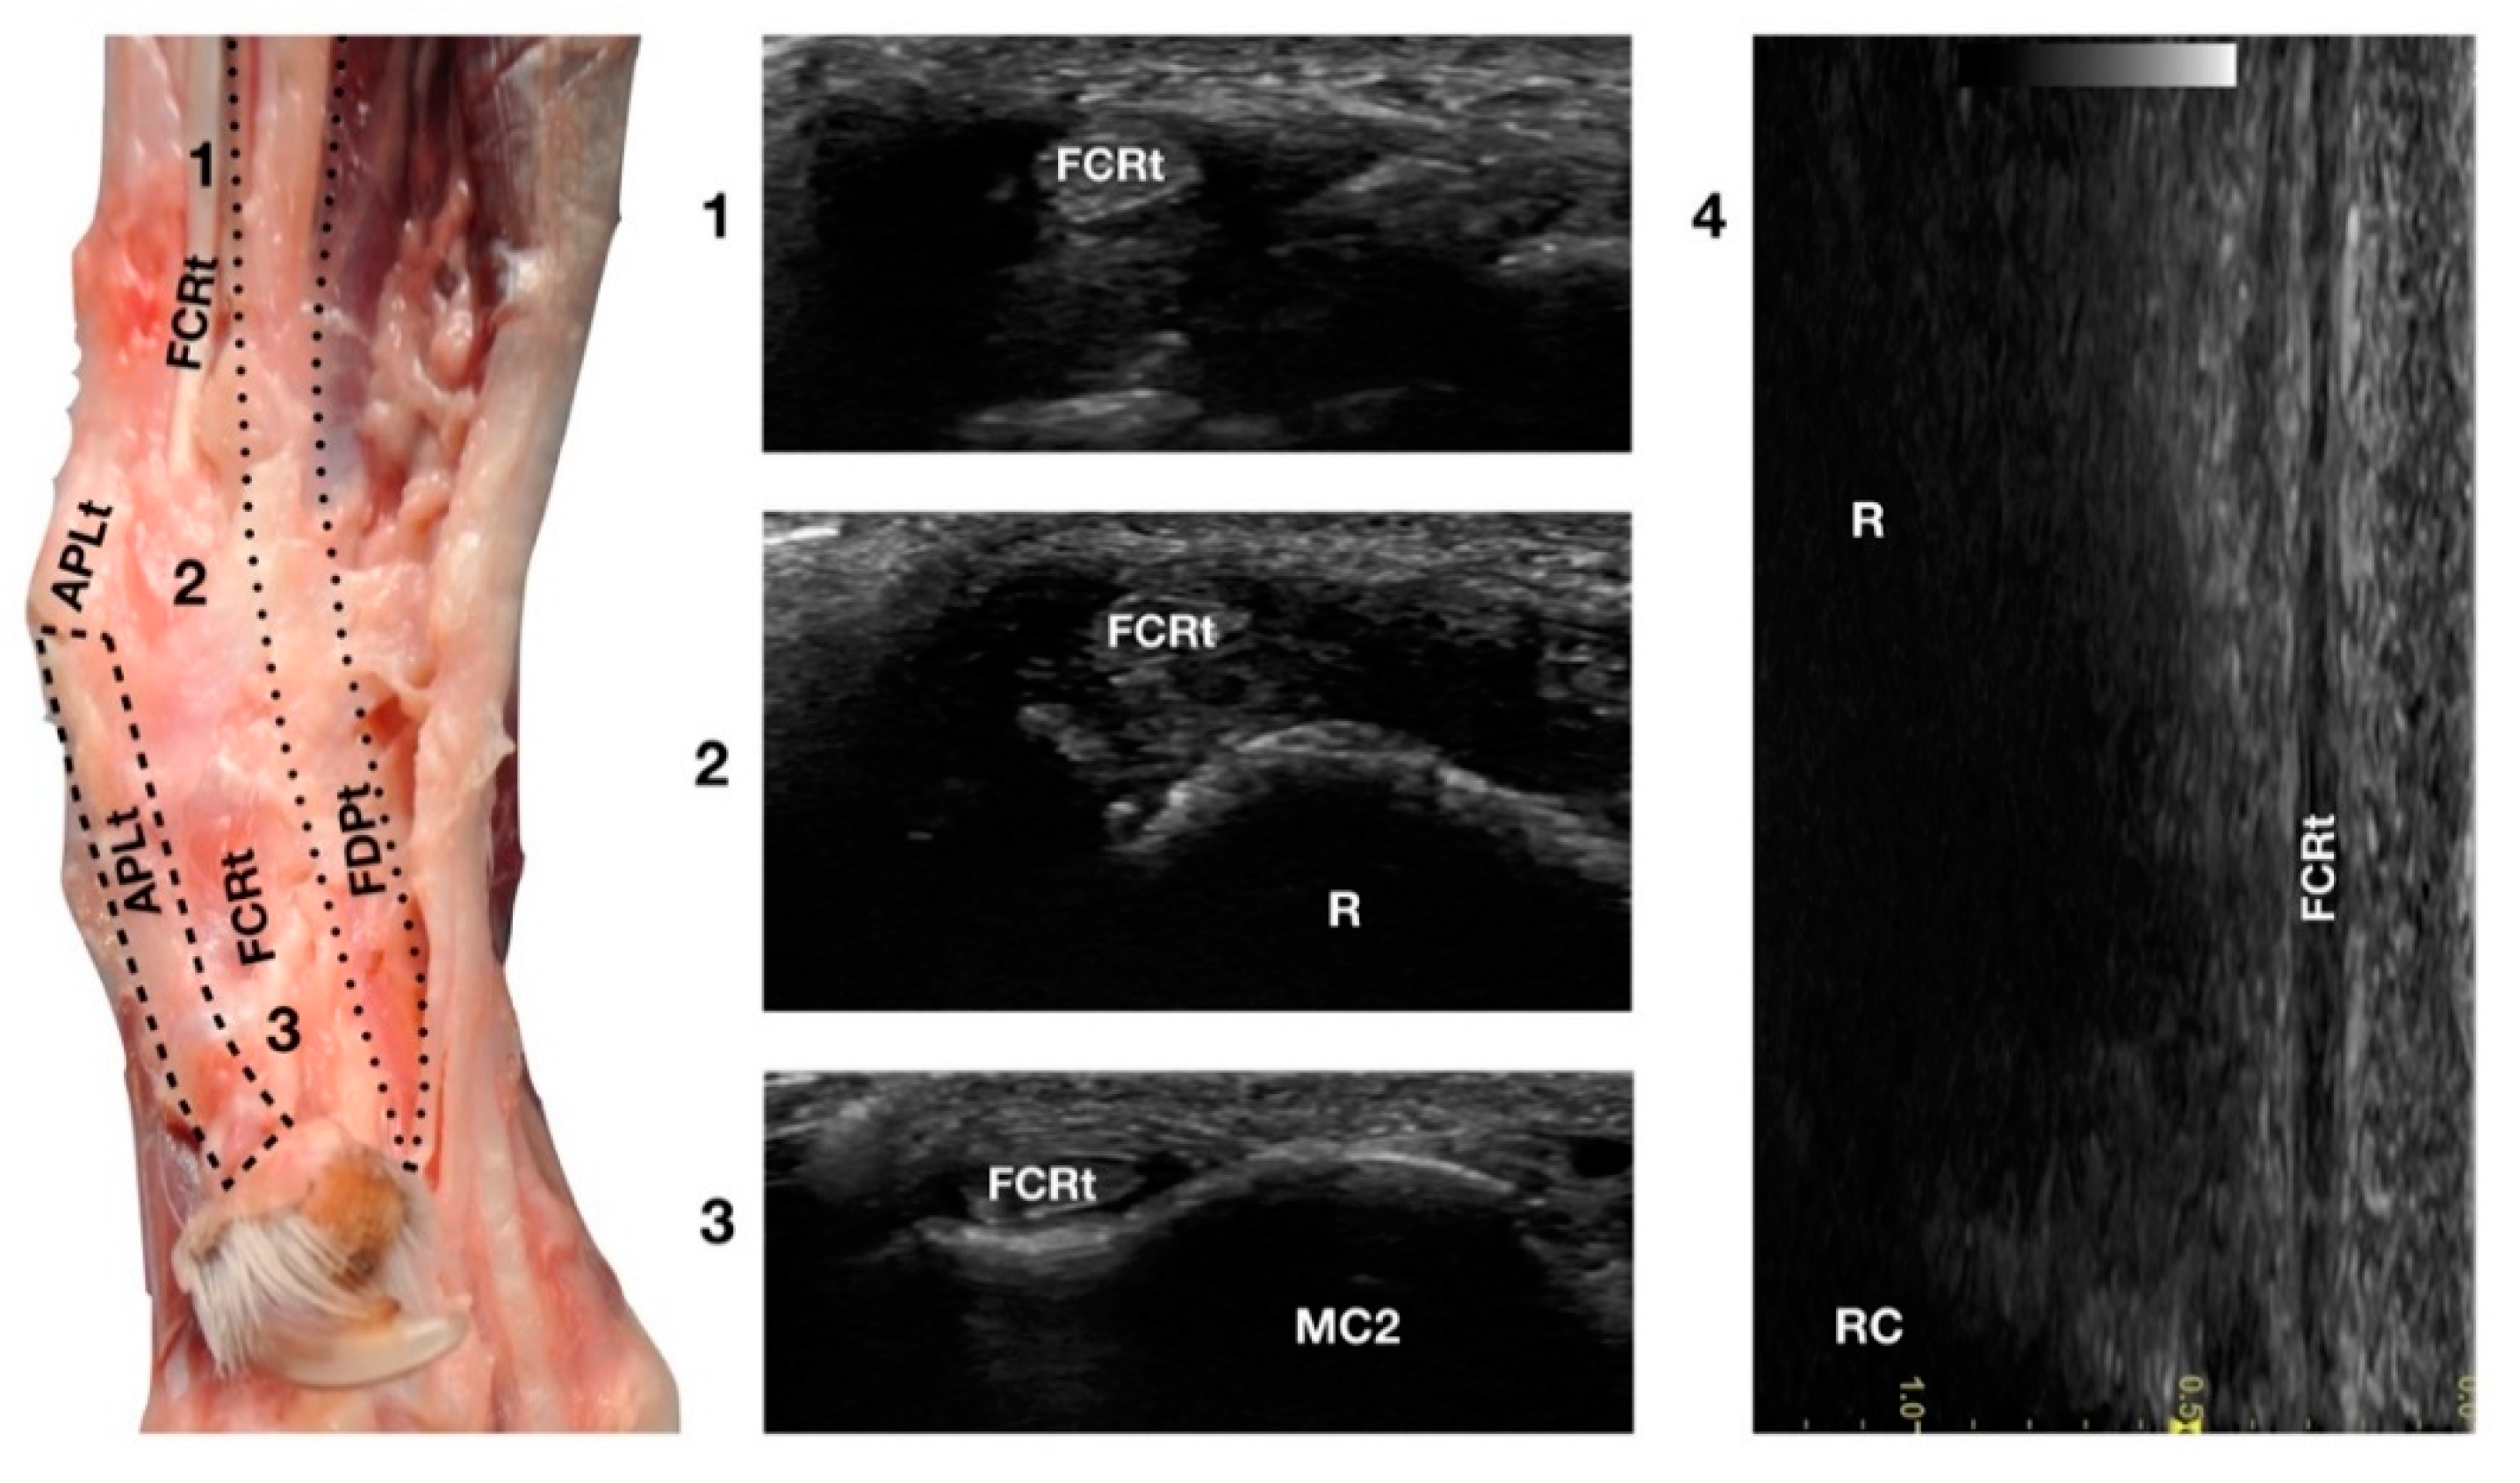

3.4.1. Flexor Carpi Radialis Tendon Ultrasonographic Anatomy (FCRt)

The Flexor Carpi Radialis was the thin tendon just palmar to the ulnar notch of the radius. It was difficult to palpate due to its small size; however, it was easy to find on ultrasound as it was the only tendinous structure in this region and was equally distanced from the APLt (medially located) and the FDPt (plantar). The FCRt was seen in the transverse scan as a small, oval to slightly rounded structure, homogeneous, and hypoechoic compared to the adjacent, more prominent tendons (FDPt and APLt). The FCR muscle lay in the medial part of the antebrachium directly under the skin and the antebrachial fascia. It covered the Flexor Digitorum Profundus muscle and appeared medial to the FDSt (Figure 1d). The thick fusiform belly merged into a flat tendon near the middle of the radius. At the flexor surface of the carpus, the FCRt ran through the medial aspect of the carpal canal enclosed in the Flexor Retinaculum, where a synovial sheath surrounded it, located superficially and medially to the FDP tendon (Figure 9).

Figure 9.

Palmaromedial carpal face centred on the Flexor Carpi Radialis (FCR) tendon. At the ulnar notch (2), the FCRt is a thin, relatively hypoechoic, oval structure surrounded by ill-defined and hypoechoic muscle fibres. Proximally, at the tenomuscular junction (1), the tendon is relatively superficial and better defined from the surrounding hypoechoic muscles. The radial surface is visible (R). At the level of the carpometacarpal joints, the tendon splits into two equal parts and becomes closer to the osseous surface of the base of metacarpal bone 2 or 3 (in this case it is MC2) where it terminates (3). On the longitudinal scan (4) obtained by aligning the probe to the palmar margin of the ulnar notch, the thin FCRt is seen as a hypoechoic structure with few visible fibrillar lines. The radial (R) and radiocarpal (RC) surfaces beneath are visible.

At the carpometacarpal joint, it split into two distinct tendons that terminated on the palmar side of the base of metacarpals II and III, very close to the proximal articular surface. On longitudinal scan, it was a thin hypoechoic tendon (due to its size), seen medially to the FDPt and palmar to the APLt. The flexion and extension of the carpus and the digits and mediolateral stressed poses were used to assess the adhesions, range of motion, and subluxations of the tendon.